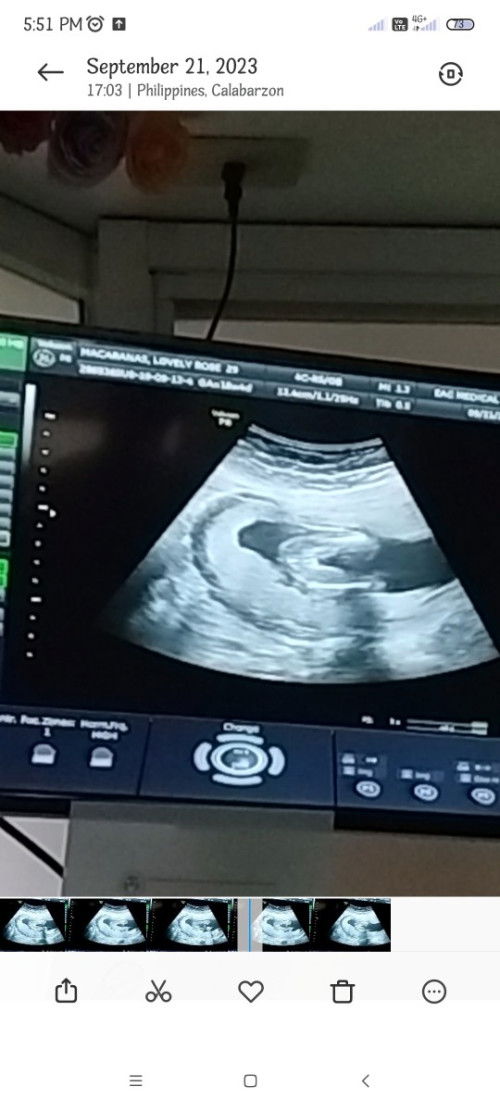

girl po sya sa ultz. Nakabuka po sya nun ultz ko kaso may nagsasabi pwede ba mabago since early pa.

Gender at 18 weeks in ultrasound